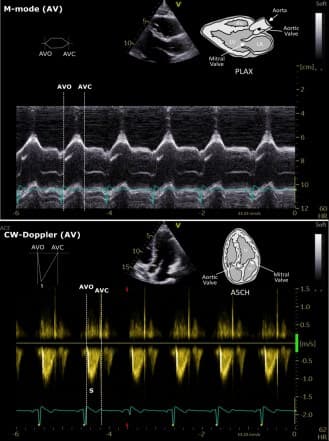

Figure 1. Echocardiographic representation of MVO/MVC and AVO/AVC.

The protocol successfully identified mitral and aortic valve timings using M-mode and Doppler imaging.

Each cardiac event is assessed using at least two echocardiographic modalities, such as M-mode and Doppler imaging.

Each cardiac event should be assessed using at least two ECHO modalities, with M-mode and flow velocity measurements (PW or CW Doppler) preferred for valve opening and closure.